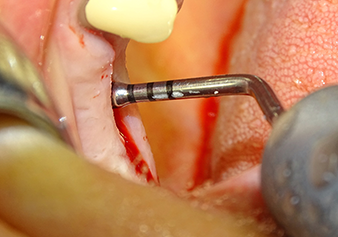

Затем, с помощью инструмента I2A (диаметр 2,0 мм), дно пазухи перфорировалось периодически и в минимально возможном диапазоне. Этот специфический пьезохирургический метод гарантирует, что мембрана Шнейдера не будет повреждена. При использовании Z25P, мембрана уже была слегка приподнята охлаждающей жидкостью, подаваемой через наконечник инструмента (рис. 3). Во избежание высокого давления в ложе имплантата, количество охлаждающей жидкости составляло не более 50%.